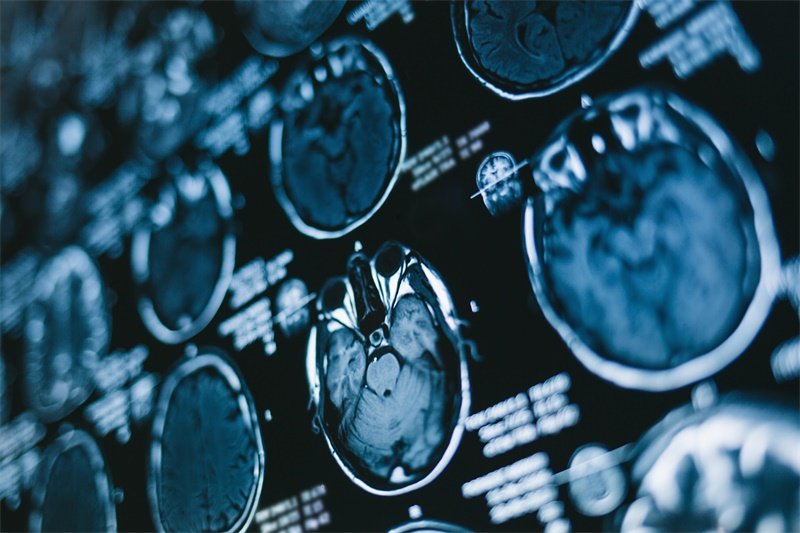

影像学检查

影像学检查是常用的诊断工具。CT扫描和MRI能够清晰显示脑部肿瘤、囊肿或其他病变。在许多情况下,医生会优先选择MRI,因为其分辨率更高,能够更清楚地显示出海马及其周围结构的变化。

另一个重要的影像学评估方法是功能性MRI,能够评估病变对大脑功能的影响。此类检查有助于确定病变的性质及其对神经功能的影响。